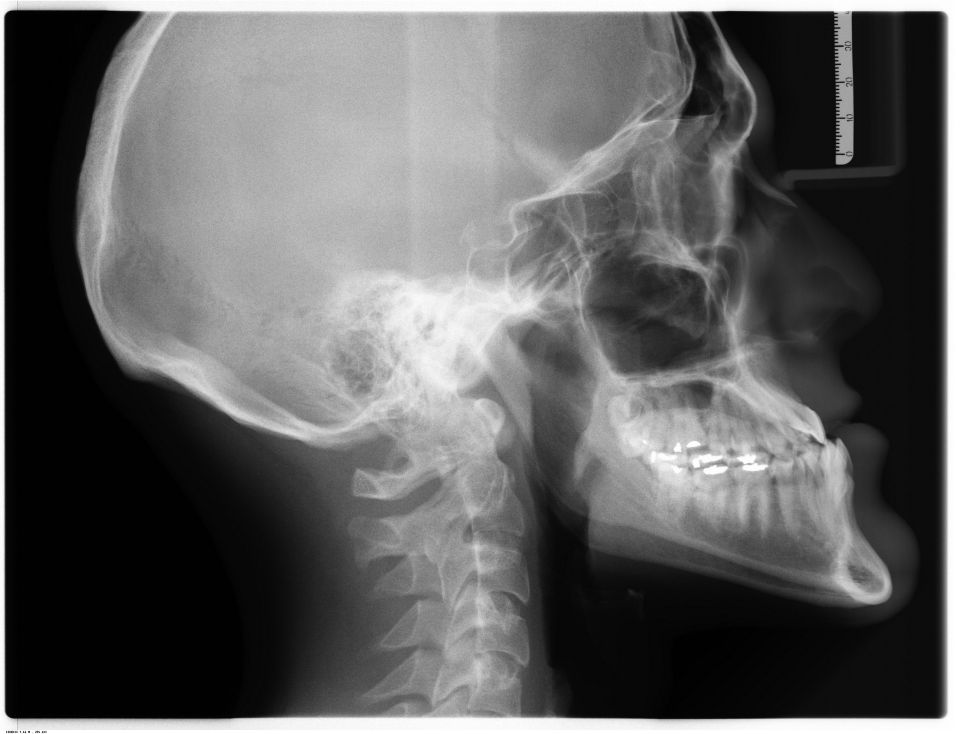

Η κροταφογναθική διάρθρωση είναι η άρθρωση που βρίσκεται μπροστά από το αυτί και ουσιαστικά ενώνει τη βάση του κρανίου με την κάτω γνάθο, επιτρέποντας στην τελευταία να κινείται και να εκτελεί τις λειτουργίες της μάσησης και της ομιλίας.

Αποτελείται από οστά, μύες και τους ενδιάμεσους χόνδρους και οποιαδήποτε δυσλειτουργία σε αυτά μπορεί να καταλήξει σε πάθηση της ΚΦΓΔ με ποικίλη συμπτωματολογία.